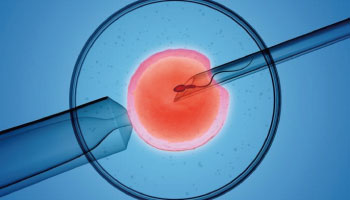

社會上對於初婚年齡漸晚與高齡孕婦的觀感已與過去大為不同了,生產時年滿35歲的婦女即是「高齡產婦」,有數據顯示,超過40歲自然懷孕率已降至5%以下。不過,準備懷孕第一步就是”養卵”,高齡雖然因卵子老化較難自然受孕,但仍可藉由飲食和作息調理、或仰賴人工生殖成功懷孕。

40歲女性自然懷孕率已降至5%以下,人工生殖活產率於受術妻年齡42歲以上也僅剩7.6%。(資料來源:生育有時鐘 助孕有補助)

政府為了鼓勵生育,妻子未滿45歲者,可至全國101家特約人工生殖機構申請試管嬰兒補助,一般家庭首次申請最高可領補助金新臺幣10萬元。

滿40歲後DNA的修復能力下降,卵巢存量耗損,檢測AMH大多處於1.0以下,且呈現非常快的下降趨勢。

40-44歲的女性裡,有29%有不孕狀況。根據美國生殖醫學協會 (ASRM)所提供的數據,超過35歲想要生育的婦女中有三分之一會遭逢到受孕的困難,而有三分之二的婦女,一旦年過40,女性可能會出現不排卵或是排卵異常現象,更容易出現染色體異常問題導致不孕、流產或畸胎,甚至高齡產婦佔產後抑鬱症患者的70%以上。